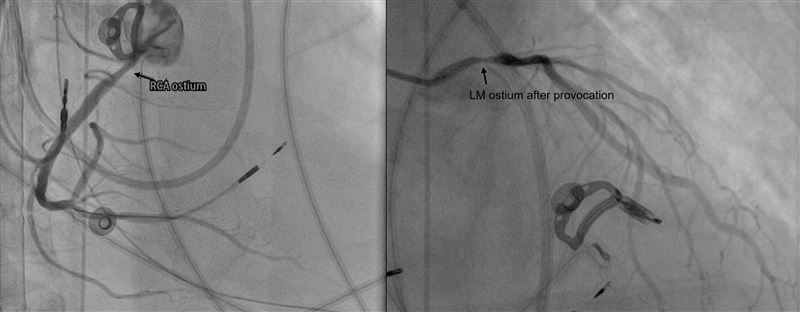

台北慈濟醫院心臟功能室主任葉冠宏,隨即仔細檢視心電圖動態變化,並考量半年內多次心跳停止的病史,安排心導管誘發測試,最終抽絲剝繭確診為罕見且嚴重的「雙側冠狀動脈痙攣」,造成冠脈劇烈收縮、血流瞬間減少甚至中斷,進而誘發致命心律不整與心跳停止。在給予抗痙攣藥物治療後,洪先生一度轉危為安並成功移除葉克膜,未料住院期間仍再度發生心跳停止,需再次即時搶救與二度葉克膜緊急裝機。

葉冠宏說,冠狀動脈痙攣普遍以藥物治療為主,但因洪先生病況嚴重,無法單靠藥物控制。為徹底降低再發風險,由心血管內、外科與胸腔外科多團隊合作,先後放置冠狀動脈支架避免病發時血管攣縮導致缺氧;並植入心臟去顫器裝置,在偵測到異常心室顫動時,自動發出電流刺激,以恢復正常心律。